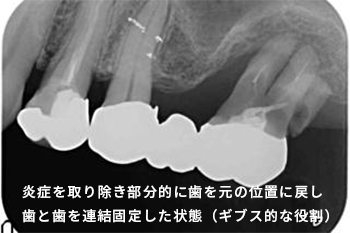

歯周組織の破壊が進んでしまうと手術(歯周外科手術)や、1本1本では噛む力に耐えられない歯と歯同士を固定するなどの処置が必要になってきます。

向かって右奥歯の根が露出してしまっています。

噛み合わせや不適切な治療や歯ブラシの仕方によって、歯周病が進行しきった状態です。

こうなってしまうと残念ながら救う手だてはありません。

前方の歯の詰め物、被せ物も決して精度高い治療とは言えません。歯周病は早期発見・早期治療が大切なのです。